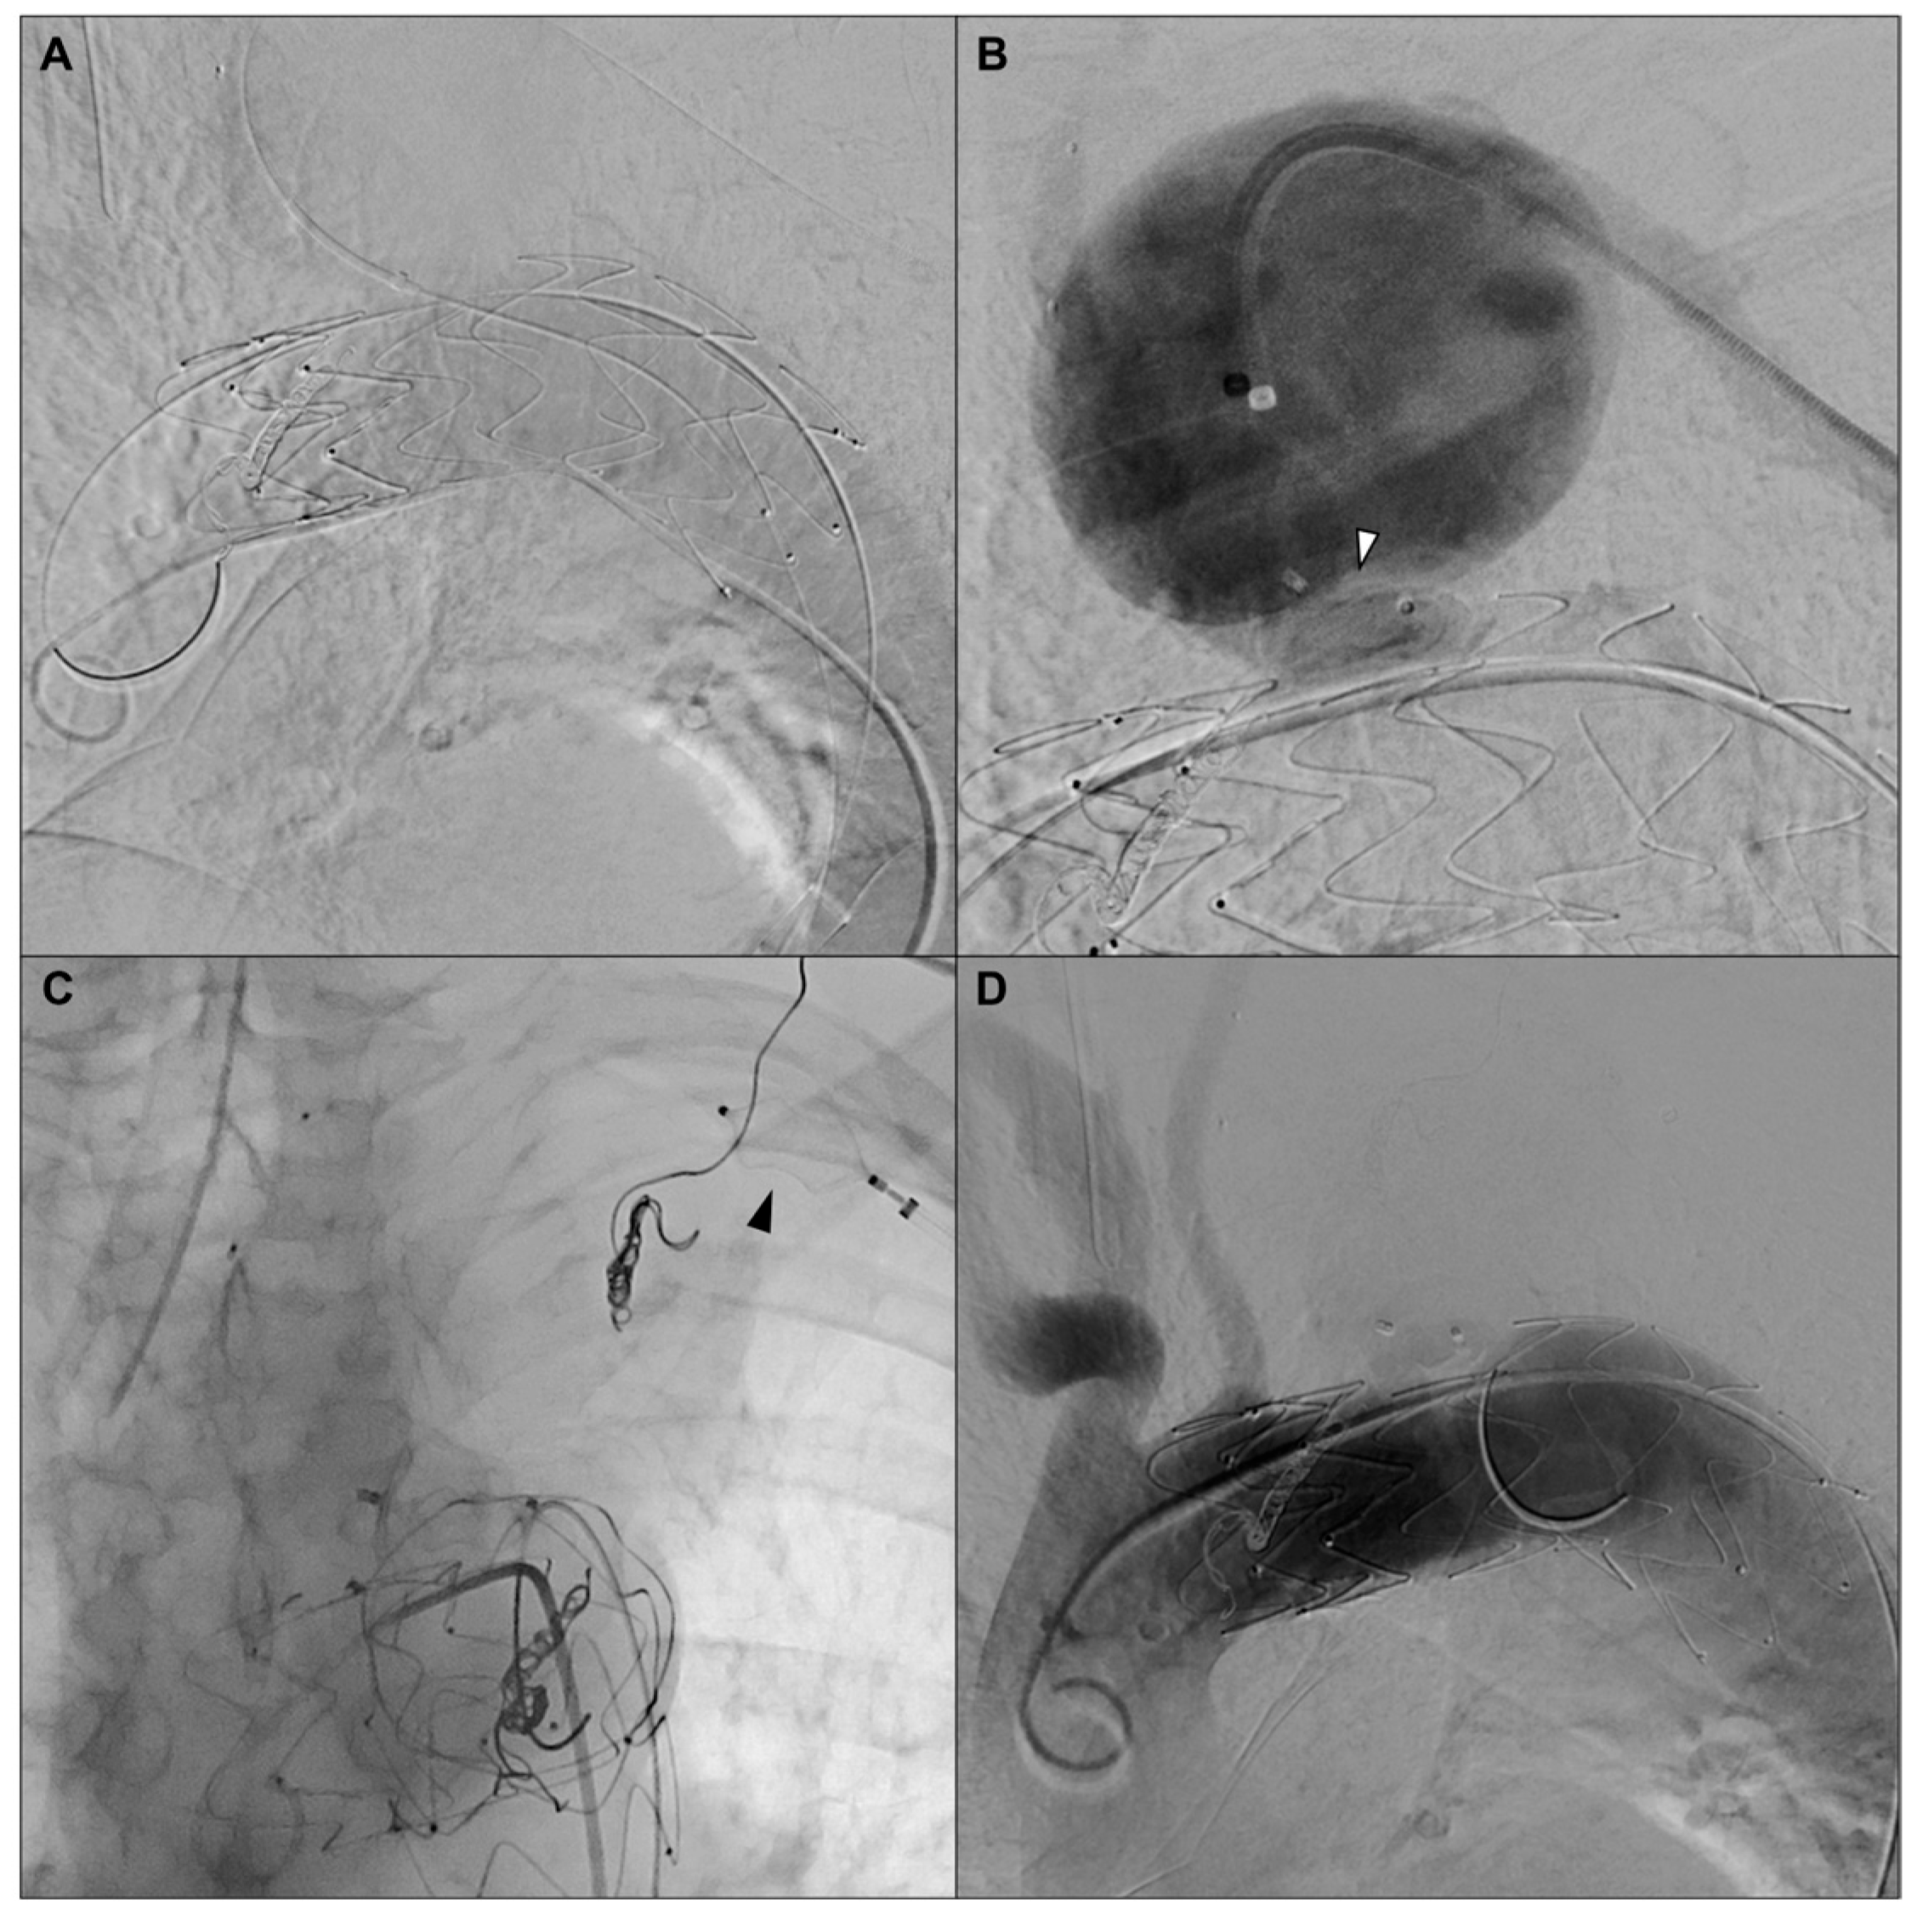

2. Case Report